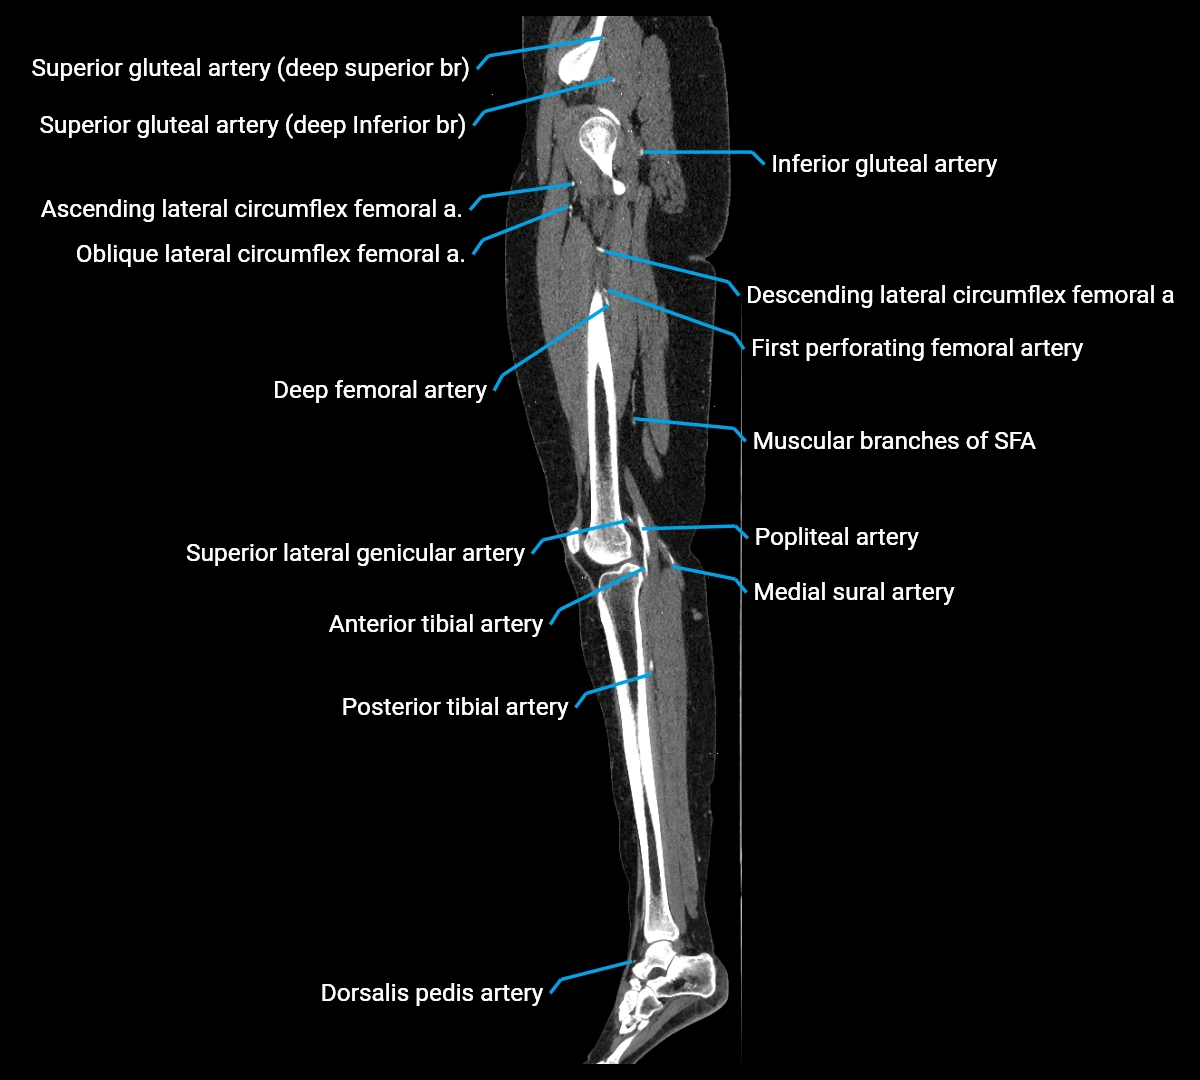

CT images

image